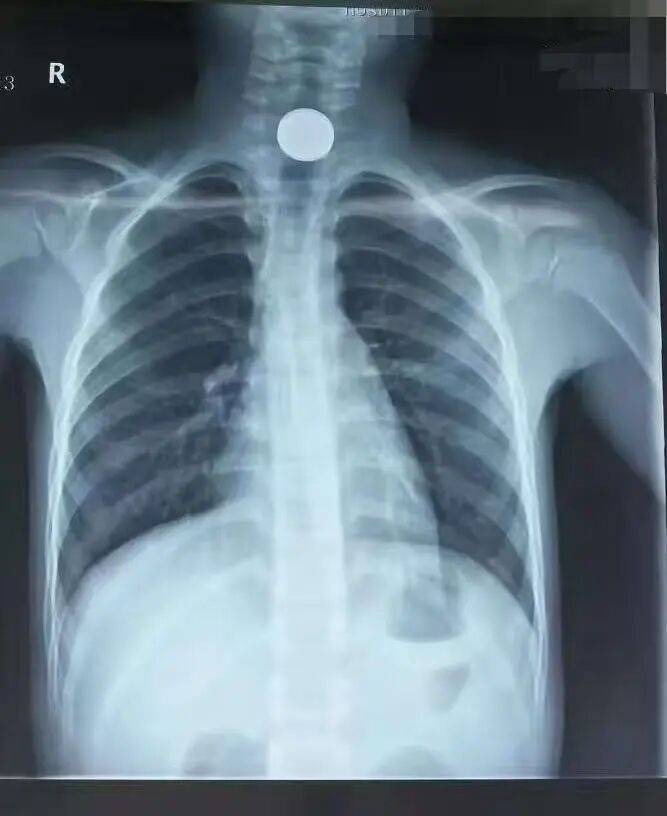

小青发现女儿最近像被戳破的气球,脸蛋上的婴儿肥以肉眼可见的速度消失。才六岁的孩子,原本肉嘟嘟的手腕突然能摸到清晰的骨头,饭桌上扒拉两口就放下筷子,夜里还总捂着肚子哼哼。起初她以为是夏天天热没胃口,直到某天给孩子洗澡时,摸到女儿后背硌手的脊椎骨,才吓得连夜抱起孩子往医院冲。拍片室里的警报声像针一样扎进耳朵。"摘项链!"医生头也不抬地递过铅衣,小青的手僵在半空——女儿从出生起就没戴过任何饰品。夫妻俩把孩子扒拉得像翻口袋,连头发丝都检查了三遍,仪器却还是固执地"滴滴"作响。换了台机器结果依旧,医生皱眉推进孩子:"先拍再说。"片子洗出来时,所有人倒抽冷气:孩子胸腔里赫然嵌着块指甲盖大的磁铁,在X光下泛着冷光,位置正好在脖颈下方,活像戴了条隐形的金属项链。手术台上,医生用内窥镜夹出磁铁时还在念叨:"再晚来几天,这东西就能穿透肠壁。"小青这才想起,上周整理储藏室时翻出的磁力片玩具,少了最中间那块星星形状的。她总以为孩子大了不会乱吃东西,却忘了六岁正是把"探索世界"理解为"放进嘴里尝尝"的年纪。病房里,看着女儿打着点滴熟睡的脸,她把家里所有小物件全塞进了带锁收纳箱,连冰箱贴都用胶带固定在高处。这事过后,小区妈妈群炸开了锅。有人说自家孩子吞过纽扣电池,有人晒出孩子误吞钢珠后的X光片。医生的话在家长圈里疯传:"5岁以下孩子的食道比吸管还细,一块磁铁就能要了命。"现在小青去朋友家做客,第一件事就是扫视茶几——花生、硬币、胸针,这些在大人眼里的小玩意,在孩子手中都可能变成凶器。那天从医院回家,她在玄关贴了张纸条:"进门前先检查口袋,别把小零件带回家。"毕竟孩子的好奇心不会停,但家长的警惕性,一秒都不能松懈。